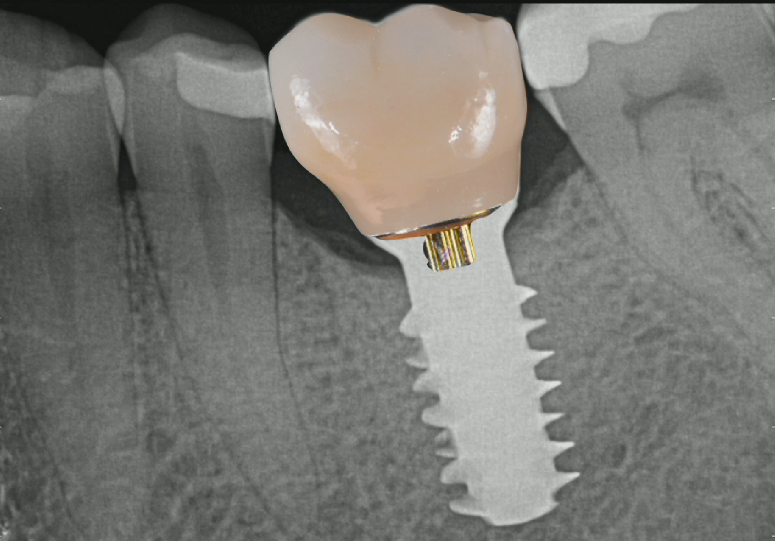

Removing a Broken Abutment Screw

Dr Sascha Jovanovic

What to do when your patient arrives in your office with panic in their eyes and the implant crown in their hands?Repairing a broken dental implant abutment screw requires careful handling and attention to detail. Here are t...